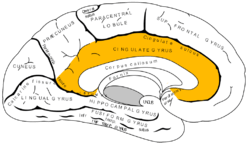

![]() Medial surface of left cerebral hemisphere, with cingulate gyrus and cingulate sulcus highlighted. | |

The cingulate cortex, a part of the limbic cortex, is a part of the brain situated in the medial aspect of the cerebral cortex. The cingulate cortex includes the entire cingulate gyrus, which lies immediately above the corpus callosum, and the continuation of this in the cingulate sulcus. The cingulate cortex is usually considered part of the limbic lobe.

Based on cerebral cytoarchitectonics it has been divided into the Brodmann areas 23, 24, 26, 29, 30, 31, 32 and 33. The areas 26, 29 and 30 are usually referred to as the retrosplenial areas.

Anterior cingulate cortex

Posterior cingulate cortex